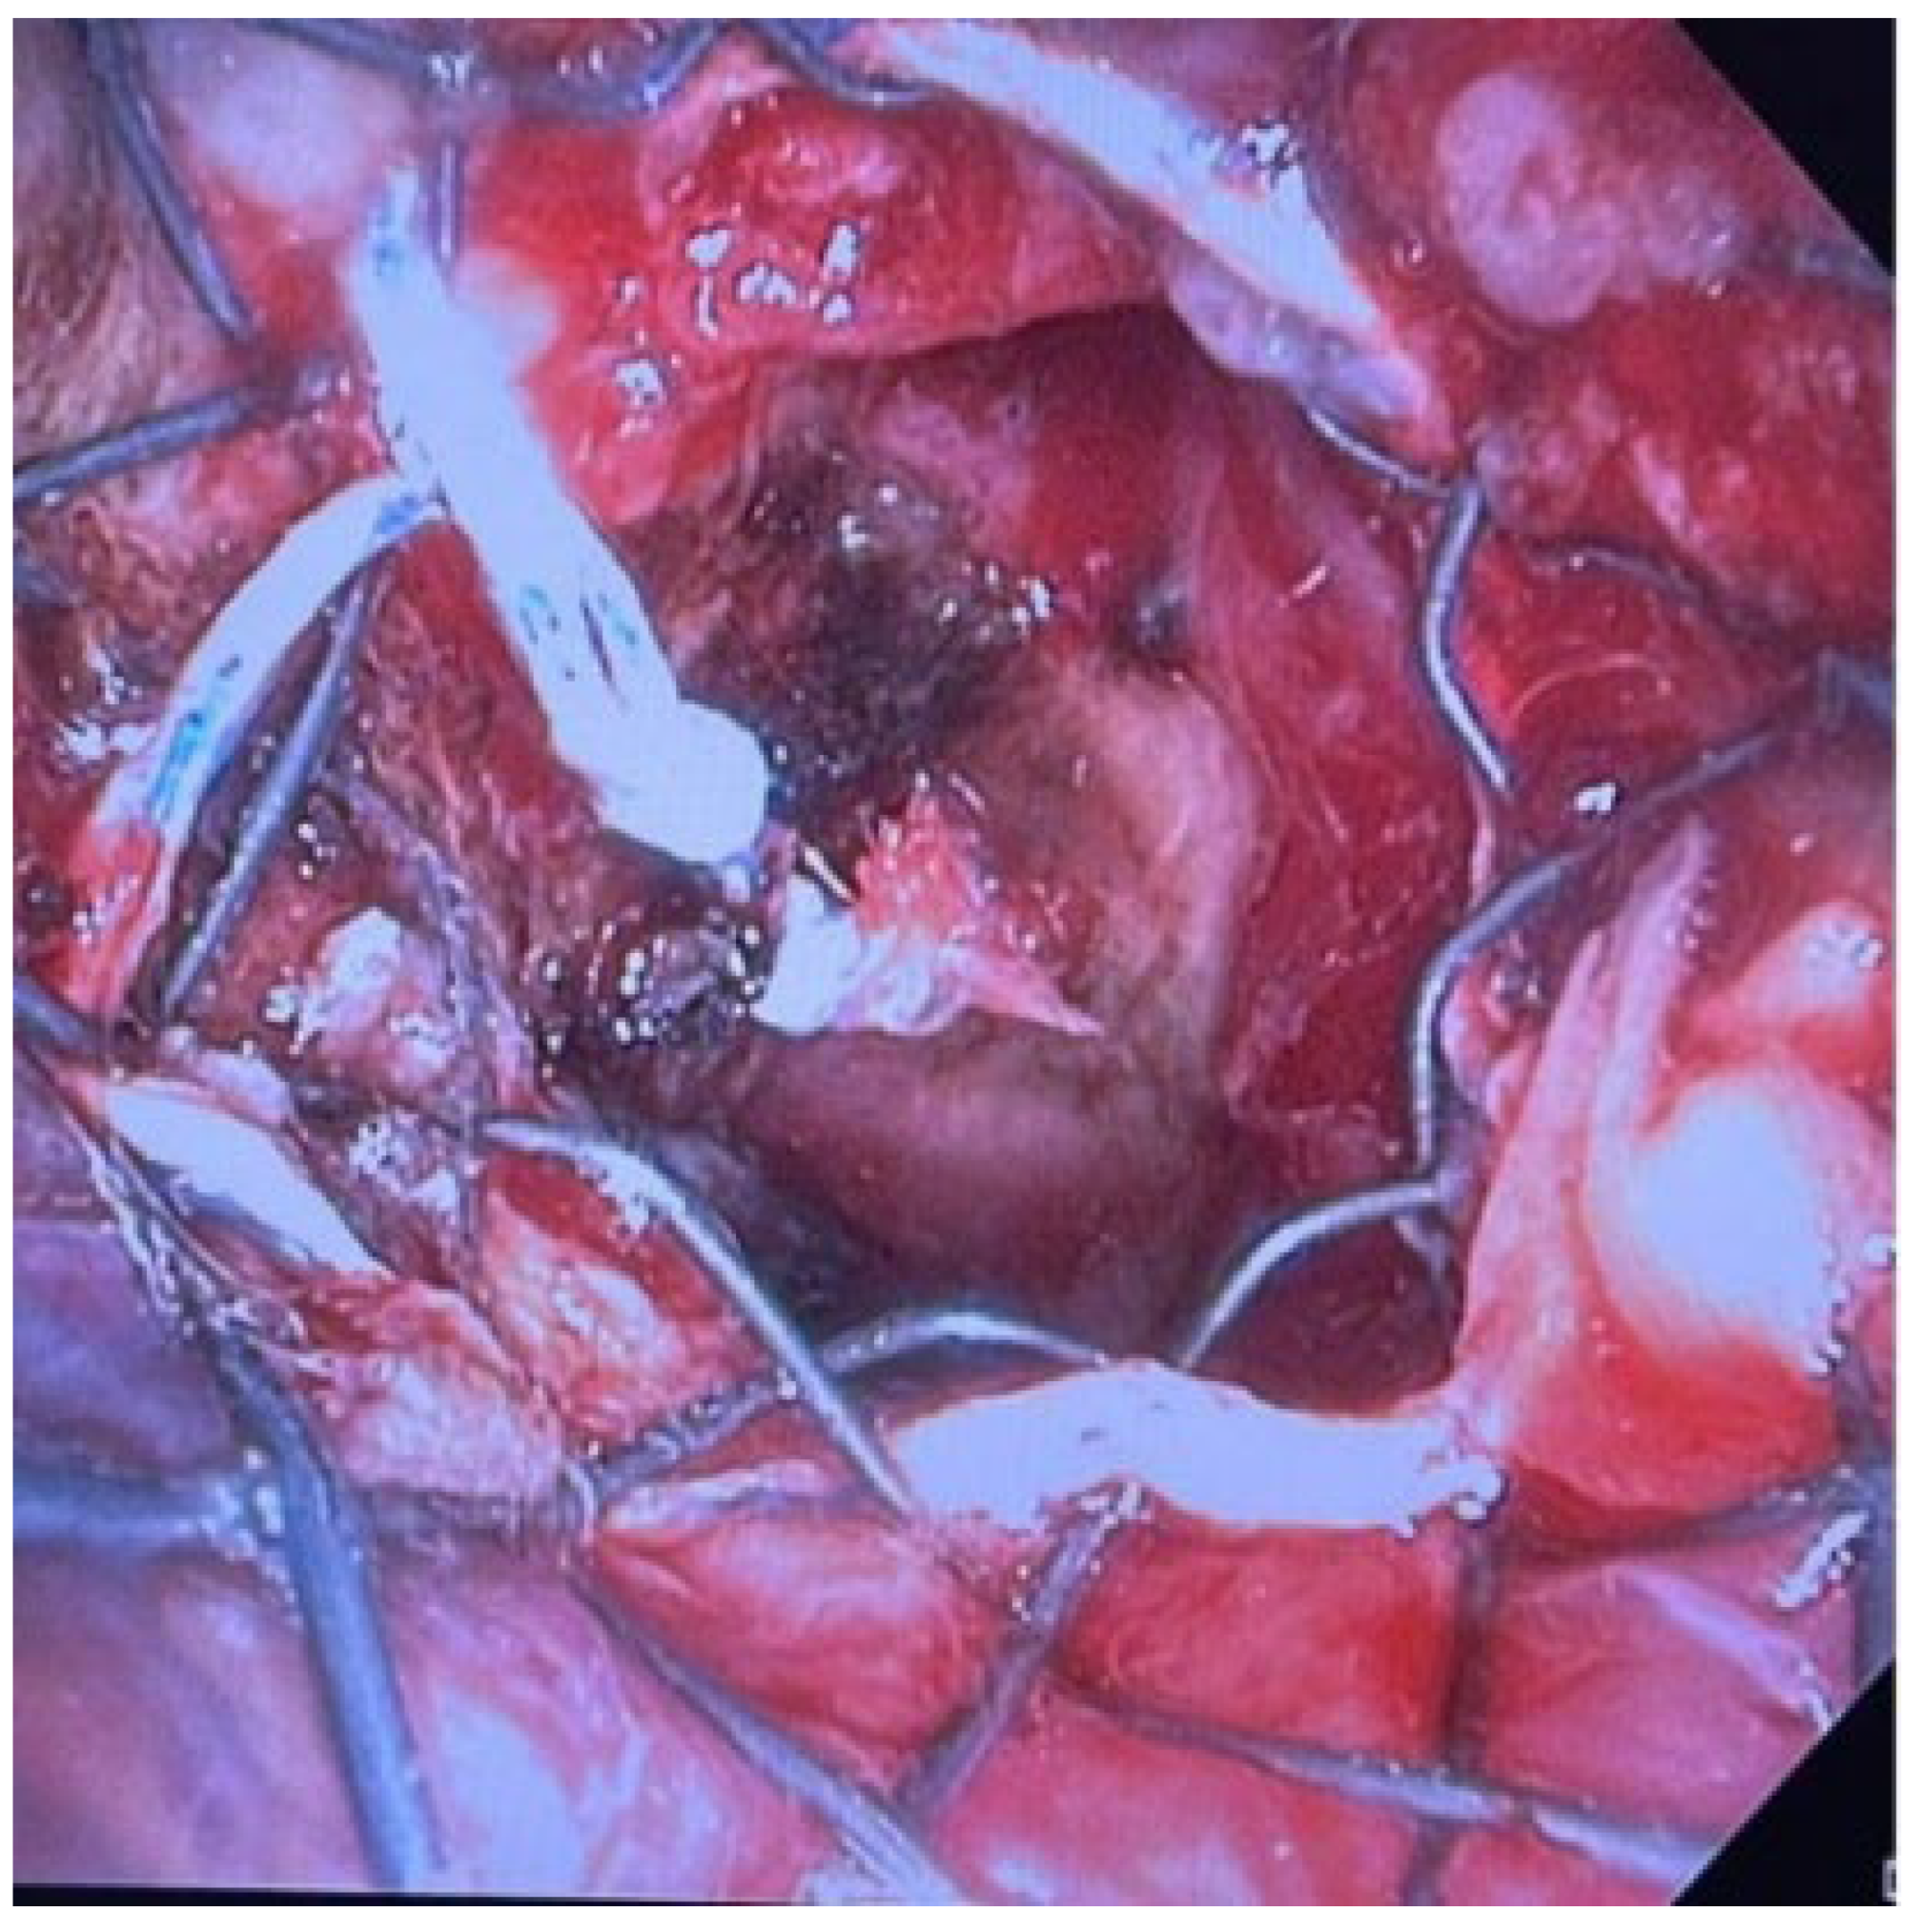

2.2. SEM Y Stent Procedural Placement in Detail